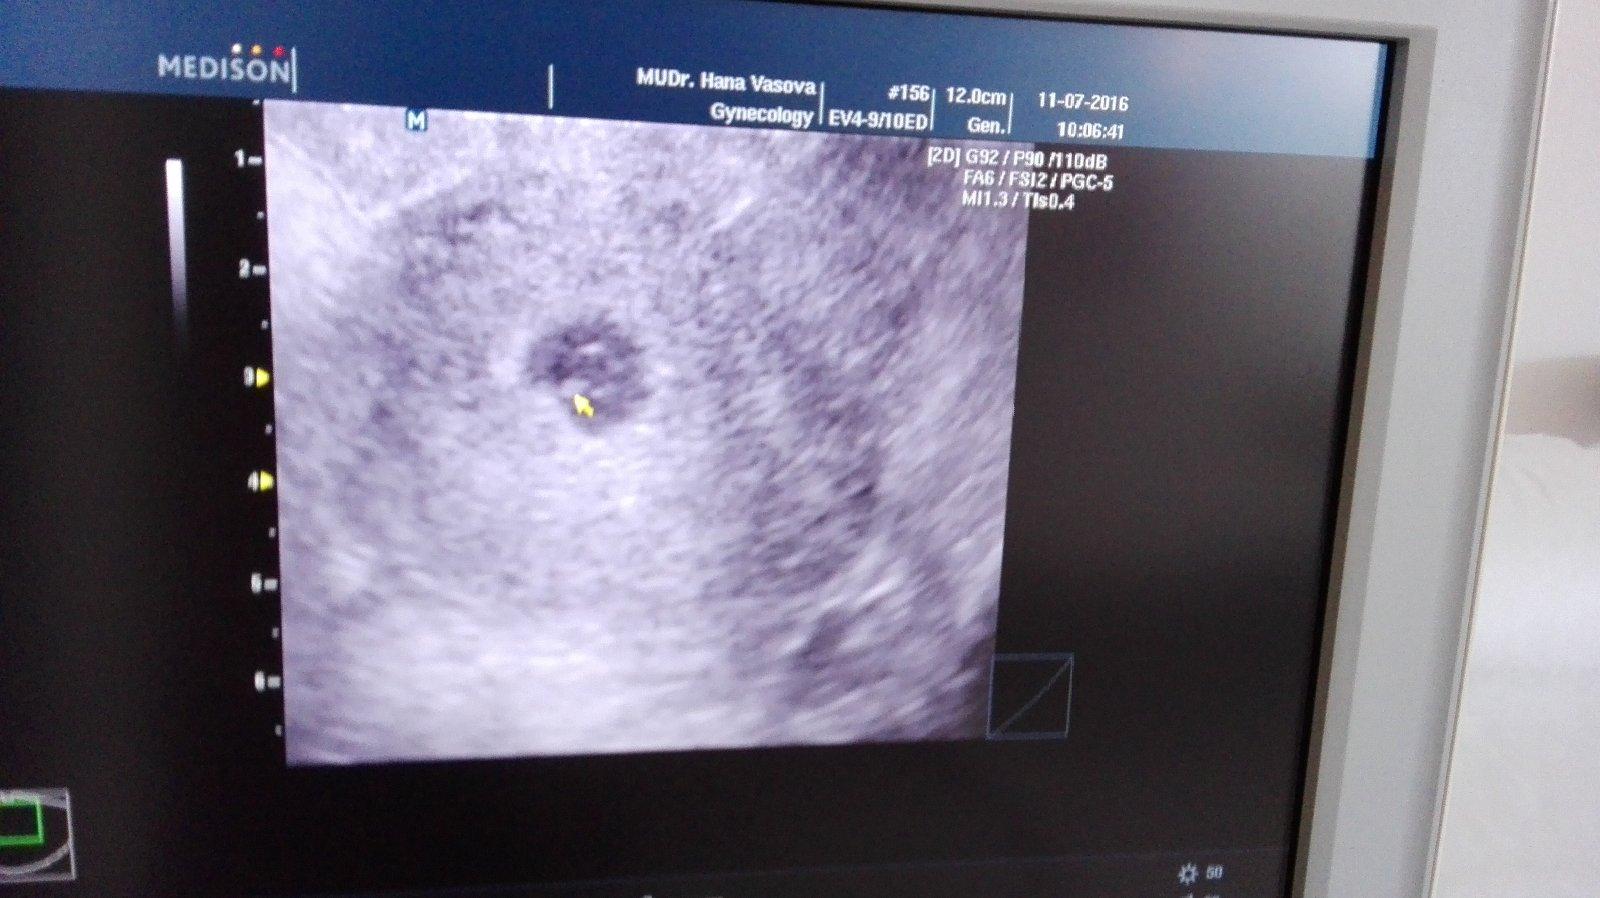

Ahojte 🙂 tak dnes potvrdené tehoenstvo od dr 🙂 ovulácia ale bola o týždeň neskôr,ako som si aj myslela,a teda zatiaľ bolo vidno len gestacny vak 0.8cm, čo podľa gyn sedí tak na 5+3tt o tri týždne sa už všetko ukáže : a už sa neviem dočkať 🙂

Ahojte. Ja som dnes vybehla pozrieť, kedy ma lekárka voľno.. Tento týždeň ešte robila, v čakárni prázdno.. Tak reku počkám a opýtam sa rovno.. Nemusím volať 😀 zrazu sa otvoria dvere, tam suseda a deti sa hneď na nu vrhli 🙂 tak kým sa rozprávali, vysvetlila som sestričke a hneď ma brala dnu 🙂 končím 6.tyzden, mimco je tam, kde má byť, o 2-3 dni väčšie, má 6,7 mm a srdiečko bije 🙂 a o 3 týždne idem na kontrolu. A keďže sa mi klepali ruky, až sa lekárka smiala, že ani tu fotku nespravím 😀 lepšia už nebude... 🙂

Dobre ranko,už som doma ..dr videl gestacny vak /samozrejme aj ja / a kontrola o týždeň v utorok 😍zobrali mi krv na hcg kvôli caru aby som im vedela povedať hodnotu a predpísal utrogestan ..o 12 hod volám výsledok 😎